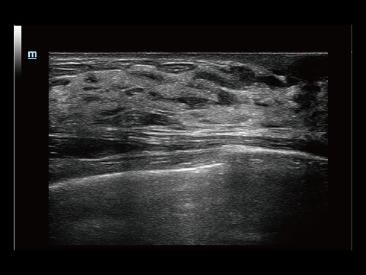

Sejak didirikan, Mindray terus mencari cara baru untuk meningkatkan keandalan diagnostik. Didukung Teknologi ZONE Sonography? terkini, platform ZST+ baru Resona 7 meningkatkan kualitas gambar ultrasound melalui pengambilan zona dan pemrosesan data saluran.